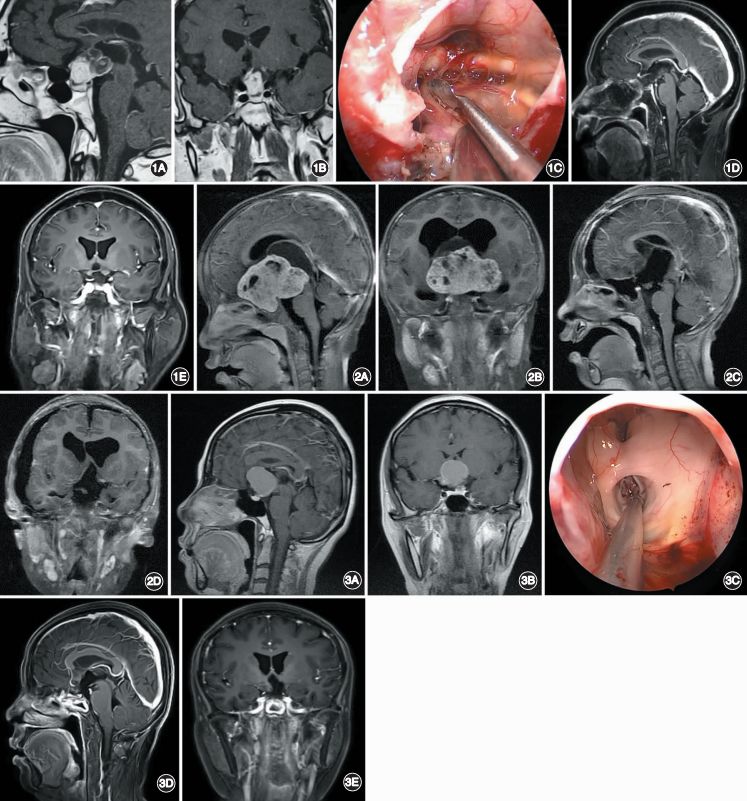

2. 鞍内-鞍上型:大多数鞍内-鞍上型颅咽管瘤的主体位于颅底中线区域,腹侧毗邻鞍底和鞍结节骨质。若选择幕上开颅手术,术中存在鞍内、视交叉下方及肿瘤上方与下丘脑之间区域三个视觉盲点;若选择神经内镜经鼻入路手术,需磨除鞍底、鞍结节、蝶骨平台骨质,可获得较宽敞的手术通道,避免从视神经之间或视神经与颈内动脉之间的间隙进行手术操作,同时可直视视交叉下方、脚间窝及第三脑室区域,不存在视觉盲点,因此可更好地完全切除肿瘤(图1),并保护血管、神经等重要结构。肿瘤完全切除后需进行牢固的颅底重建。但是,对于向两旁生长过多、超过颈内动脉分叉以外较多的鞍内-鞍上型颅咽管瘤,不主张选择神经内镜经鼻入路手术,因为经此入路向外侧区域进行操作时术者的视角受限;主张选择幕上开颅显微手术(图2),手术入路包括:经额外侧入路、经额底纵裂入路及经翼点入路。

3. 鞍上型:是否选择神经内镜经鼻入路切除肿瘤,关键在于观察经鼻抵达肿瘤腹侧的手术通道角度是否通畅、手术空间是否足够。若肿瘤主体位于颅底中线区域,且位于鞍背前方,神经内镜经鼻入路可从垂体和视交叉之间抵达肿瘤腹侧,且手术通道的角度和空间都适合,建议采取神经内镜经鼻入路手术(图3)。若肿瘤向两侧延伸过多,或肿瘤主体位于鞍背后方(图4),或肿瘤向鞍背后下方生长较多时,则不适合采用神经内镜经鼻入路手术,建议采用幕上开颅显微手术切除肿瘤,因为神经内镜经鼻入路手术时存在视角受限或手术通道空间狭窄的问题。

图1. 鞍内-鞍上型颅咽管瘤患者的影像学资料和术中所见。A,B.术前矢状位(A)和冠状位(B)增强 MRI显示肿瘤位于鞍内-鞍上区;C.神经内镜经鼻入路可直抵肿瘤腹侧,清晰可见鞍内、视交叉下方及肿瘤与下丘脑之间的区域,同时垂体和视交叉之间的空隙足以切除肿瘤;D,E.术后矢状位(D)和冠状位(E)增强 MRI可见肿瘤完全切除。图2. 向两侧生长过多的鞍内-鞍上型颅咽管瘤患者的影像学资料。A,B.术前矢状位(A)和冠状位(B)增强 MRI显示肿瘤位于鞍内-鞍上区,且向两侧生长过多;C,D.经额外侧入路切除肿瘤后,矢状位(C)和冠状位(D)增强 MRI显示肿瘤完全切除。图3. 鞍上型颅咽管瘤患者的影像学资料和术中所见。A,B.术前矢状位(A)和冠状位(B)增强 MRI显示肿瘤位于鞍上区;C.神经内镜经鼻入路可直抵肿瘤腹侧,肿瘤切除后可见第三脑室内脉络丛和中脑导水管上口;D,E.术后矢状位(D)和冠状位(E)增强 MRI显示肿瘤完全切除。